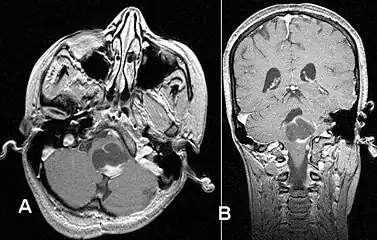

- Stereotactic MRI brain scan showing a recurrent postoperative brain stem cystic pilocytic astrocytoma.

- Pilocytic astrocytoma in the hypothalamic region.

- Sagittal T1-weighted MRI showing a well-circumscribed hypointense mass in the tectum (presumably a tectal plate glioma). These lesions are a distinct subset of pilocytic astrocytoma which present with hydrocephalus typically in 6 to 10 year-olds and are rarely progressive lesions. When imaging is characteristic, a biopsy is usually not performed because of the risks to adjacent structures, often shunting to relieve intracranial pressure is the only treatment required.

- T1-weighted coronal MRI image postcontrast showing heterogeneous contrast enhancement within the presumed tectal plate glioma